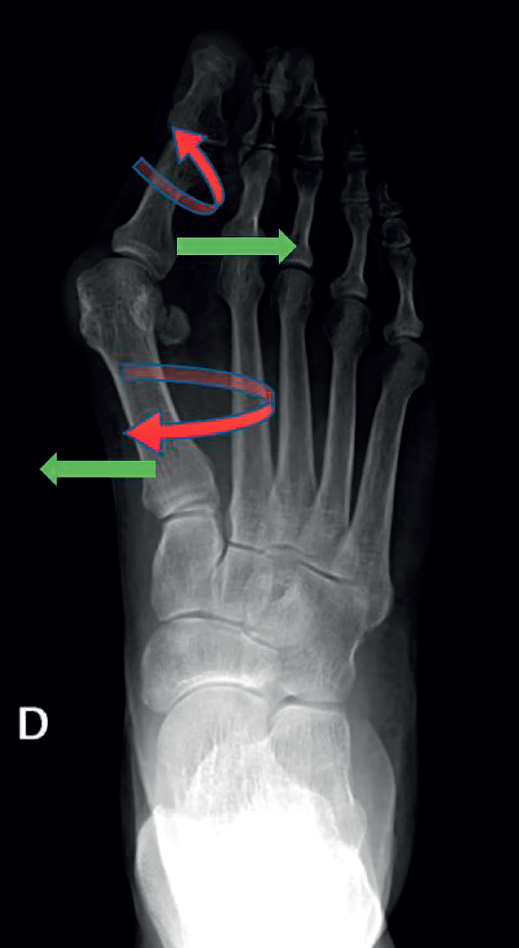

Consiste en una alteración de la articulación metatarsofalángica (MTF) del primer radio del pie. Es una deformidad compleja que incluye, por un lado, la desviación del primer dedo del pie (hallux o dedo gordo) hacia el resto del pie, alejándolo de la línea media del cuerpo (abducto), con una rotación en el plano frontal (pronación del primer dedo). Por otro lado, también incluye la desviación del primer metatarsiano (M1), aproximándolo a la línea media del cuerpo (varo de M1), con una pequeña rotación externa, como se puede ver en la Figura 1. Esta modificación de la articulación afecta a todas las estructuras anatómicas próximas, como la cápsula articular, los ligamentos colaterales, los huesos sesamoideos, la musculatura intrínseca y la extrínseca)(2).

Esta técnica suele ser complementada con una osteotomía de falange proximal del primer dedo (Akin) para corregir la rotación del primer dedo. Algunos ejemplos de pacientes intervenidos en nuestro centro se recogen en la Figura 3.

Figura 3. Ejemplos de hallux valgus intervenidos en nuestro centro: A: pie izquierdo pre-intervención quirúrgica (IQ); B: pie izquierdo post-IQ; C: pie derecho pre-IQ; D: pie derecho post-IQ.